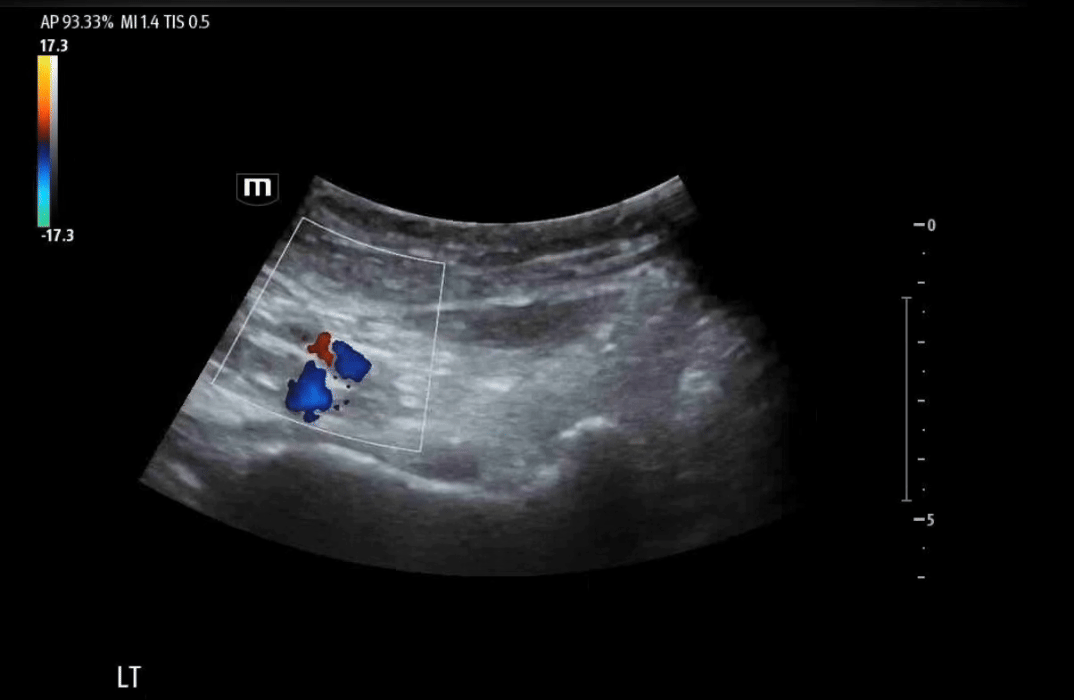

Clips from our PENG block for this patient:

Color flow to confirm femoral neurovascular bundle.